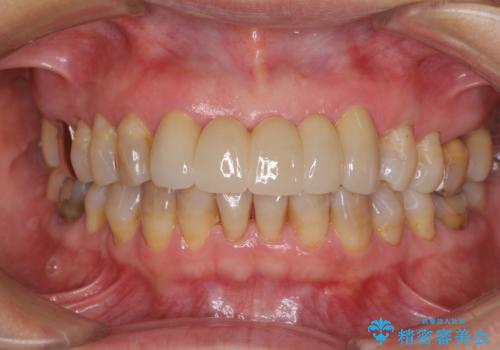

- アンバランスな色や形、歯肉ラインの黒い縁が目立ってしまったブリッジの作り直しを希望して来院された患者様です。

自然な仕上がりとするため、金属を使用しないオールセラミックブリッジにより補綴治療を行うこととしました。

装着されていたブリッジは、支台となっている歯と欠損している歯で色が大きく異なっていましたが、オールセラミックとしたことで、全体的に色調の整った仕上がりとなりました。

歯肉ラインがきれいに整い、患者様には大変満足していただきました。